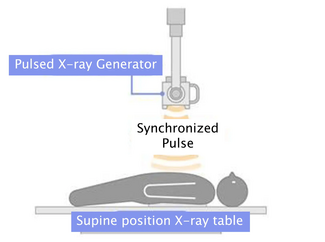

Severe pulmonary hypertension, thickening of tricuspid leaflets with vegetation on the ventricular side, and severe aortic valve thickening and stenosis were noticed on echocardiogram. A flow from aorta to right atrium was also seen. Transesophageal echocardiogram confirmed an aortic annular abscess with aorto-right atrial shunt.

At surgery, a bicuspid aortic valve with heavy calcification and acute infectious debris was noted. There was also an inflamed and indurated area found in the right atrium, which was debrided. The aorta to right atrial fistula was repaired with bicameral pericardial patch. The aortic valve was replaced with a bioprosthesis.

At surgery, a bicuspid aortic valve with heavy calcification and acute infectious debris was noted. There was also an inflamed and indurated area found in the right atrium, which was debrided. The aorta to right atrial fistula was repaired with bicameral pericardial patch. The aortic valve was replaced with a bioprosthesis.